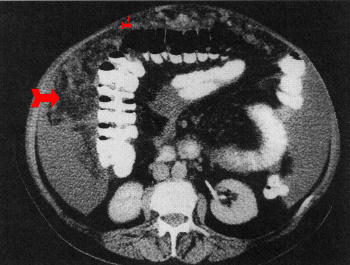

שאתות וציסטות - השאתות הן לרוב משניות ומקורן במערכת העיכול או באיברי המין (גניטליה). ציסטות ראשוניות או אנומליות בכלי דם מתגלות לעתים במקרה בניתוחים מסיבות אחרות. תצלום 3.2 מציג שאת משנית באומנטום (Omental cake).